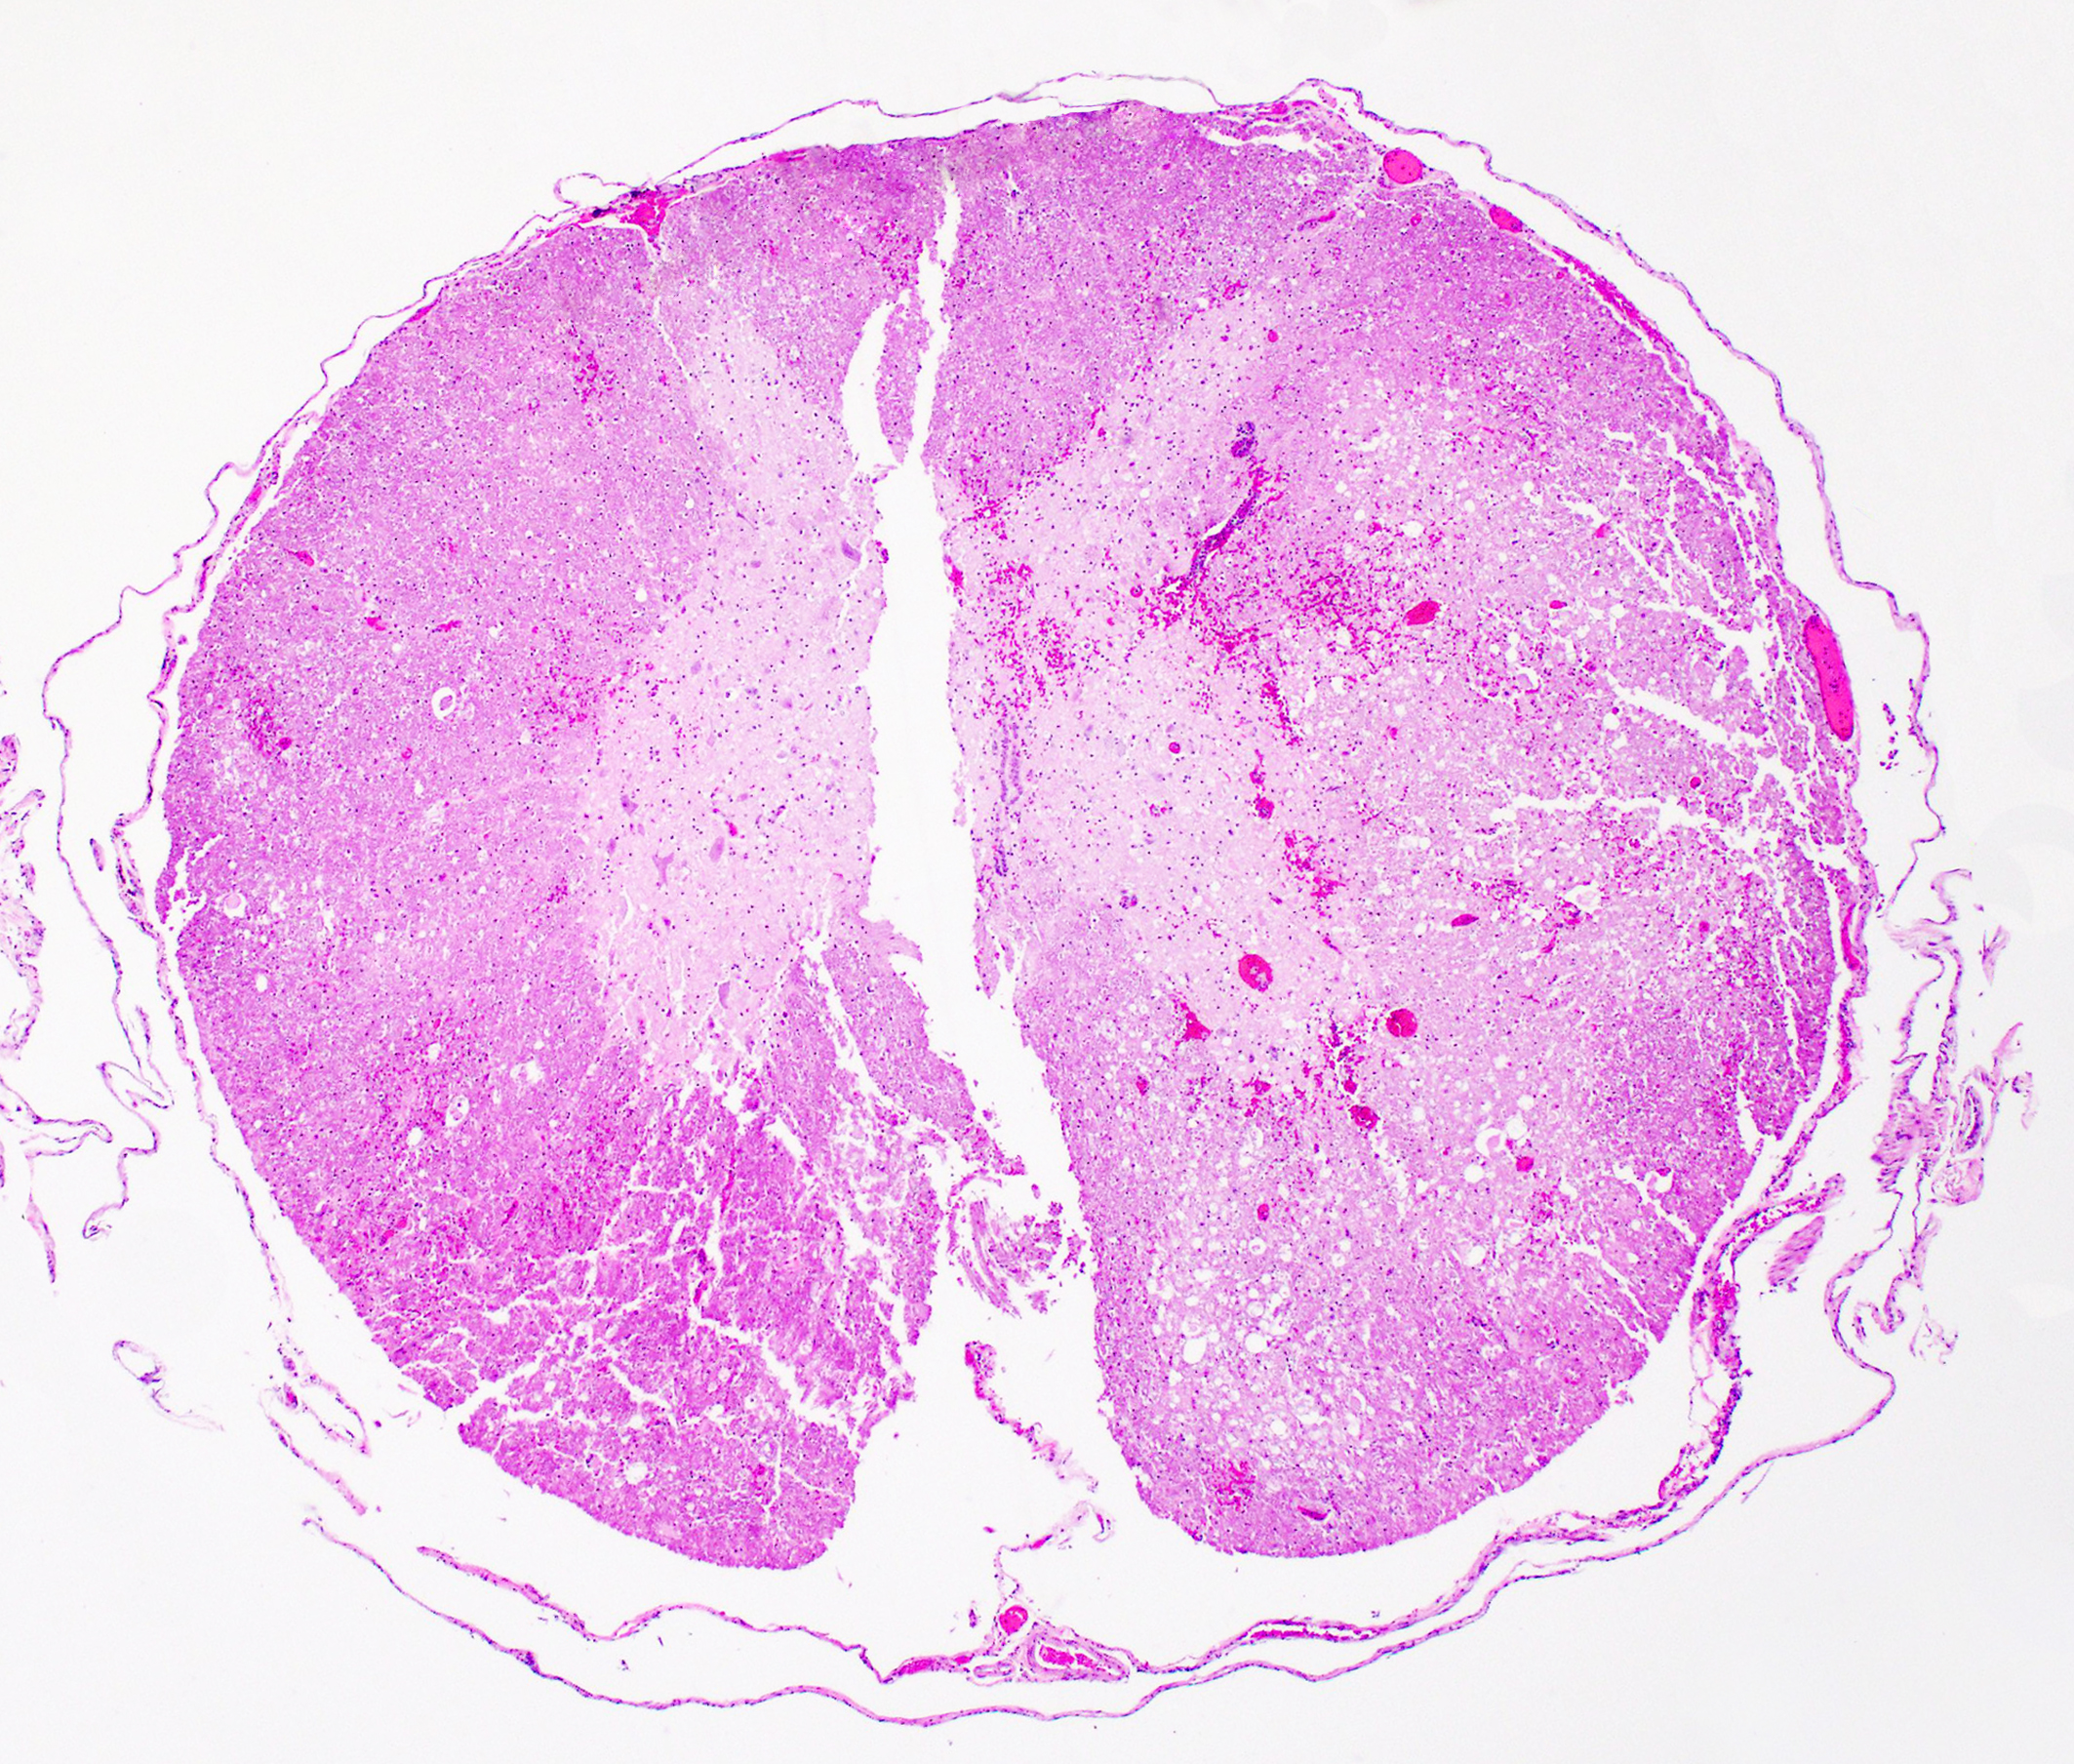

T11 Vertebra: Replacing and effacing the medullary cavity and multifocally infiltrating and destroying the cortical bone to extend into the vertebral foramen and local paravertebral stroma is a densely cellular, unencapsulated, poorly demarcated, infiltrative mass comprised of closely packed round cells arranged in sheets supported by a fine, fibrovascular stroma. Neoplastic round cells have distinct cell borders, moderate amounts of pale eosinophilic cytoplasm with inconsistent perinuclear clearing (Golgi apparatus), and single nucleus. Nuclei are round, paracentral to eccentric, and have coarse to clumped chromatin and up to one prominent nucleolus. Anisocytosis and anisokaryosis are marked, with up to 6-fold difference in nuclear side, as well as occasional megakaryocytic cells and bi- and multinucleated neoplastic cells. Fifteen mitotic figures are seen in 10 [40x x FN22] HPF. Infrequent individual necrotic neoplastic cells are scattered throughout the tumor. Approximately 40% of the vertebral cortical bone is lytic due to tumor infiltration and is multifocally replaced by reactive fibroblasts and a fibrocollagenous stroma. The retained cortical bone is multifocally thinned and there is resorption and remodeling characterized by scalloped surfaces and shelves of woven bone bordered by neoplastic cells and reactive fibroblasts. At the periphery of the tumor and within regions of bone resorption there are minimal hemorrhages.

On gross examination of affected bones, the trabecular bone/medullary cavity are replaced and filled by a soft, fleshy to gelatinous, dark red to grey-pink nodules and masses.6,29 Histology shows focal or locally extensive solid tumors of densely packed neoplastic plasma cells arranged in sheets, cords, and packets that replace the hematopoietic cells and adipose tissue of the medullary cavity and are supported by a fine fibrous stoma.6,7,16,29,32 Cortical bone destruction with/or without local soft tissue invasion can be seen.29 Cellular features of plasma cell differentiation include round cells with moderate to large amounts of amphophilic to basophilic cytoplasm with perinuclear clearing (Golgi apparatus).7,9,16,18,22,30,32 Nuclei are paracentral to eccentrically placed with clumped chromatin that aggregate in the center or along the nuclear membrane ("clockface" pattern).7,9,16,18,22,32 Mott cells with prominent cytoplasmic vacuoles (Russel bodies) containing immunoglobulins and may result from altered intracellular protein transport.18,22,32 Due to differences in stain protocols, these vacuoles can range from semi-clear, to light blue, to pink.22,32 "Flame cells" are characterized by an outer rim of densely purple or eosinophilic cytoplasm,32 with light to bright pink projections/blebs or fringe due to accumulation of immunoglobulins.7,22,23,29 Less well-differentiated tumors display a wider range of cellular and nuclear pleomorphism, variable nuclear-to-cytoplasmic ratio, increased numbers of binucleate and multinucleated cells, and lack of Golgi perinuclear clearing.29,32 Plasma cell tumors infrequently have intratumoral light chain amyloid (AL-amyloid).6,7,18,19,22,24,30,32 Erythrophagocytic plasma cell tumors have been described.3,26 With less differentiated forms, immunohistochemistry (IHC) can be useful to rule-out other round cells tumors. In dogs, MUM1 is the most specific marker for plasma cell tumors.6,7,9,16,24,26,31-34 Multiple myeloma oncogene 1 (MUM1) is an interferon regulatory transcription factor involved in immunoglobulin light-chain re-arrangement and production of plasma cells.16,22,24,31,32 Additional tumors that can infrequently be immunoreactive to MUM1 include B-cell lymphoma and anaplastic lymphoma.24,32 Less consistently plasma cell tumors will stain with lambda and kappa light chains, Ig heavy chains, CD79a, and CD20.9,19,22,24,32,33 In one study of canine plasmacytomas, 93.5% of tumors were immunoreactive to MUM1, while only 56.2% and 19.4% of tumors were reactive with CD79a and CD20, respectively.24 In a case series in cats, 32% of MRDs were immunoreactive to CD79+.19 Methyl green pyronine histochemical stain inconsistently highlight plasma cells.9

Participants immediately recognized a round cell neoplasm replacing the vertebral marrow cavity. Because participants had only the H&E slide to review prior to conference, and because the neoplastic cells displayed atypia without uniformly classic plasma cell morphology, conference goers agreed that they could not definitively diagnose a plasma cell tumor from the slide alone. As such, the JPC elected to diagnose a lymphoma, which is reflected in the morphologic diagnosis. This decision also reflects the fact that, in addition to the morphology of the neoplastic round cells, lymphoma is the most common hematopoietic neoplasm, as the most common malignancy in ferrets (islet cell tumors, which rarely metastasize in this species, notwithstanding). However, when the full clinical, gross, and laboratory context was revealed, including vertebral osteolysis, splenic involvement, monoclonal gammopathy, classic cytologic findings, and systemic plasma cell proliferation, the case aligned well with multiple myeloma as the final diagnosis. This contrast between what can be stated from the H&E slide alone and what can be concluded from a more comprehensive data set provided an excellent teaching moment on the importance of a full diagnostic work-up in cases such as this.

The slide also contained several key osseous features, including resting and reversal lines, microfractures, reactive fibrosis, and numerous osteoclasts. All of these are consistent with an aggressive, lytic bone process. Although not present on the H&E slide, the contributor provided some excellent gross and additional histologic images that showed compression myelopathy of the affected area of thoracic spinal cord, serving as a correlation to the pathogenesis of the clinical presentation in this case.